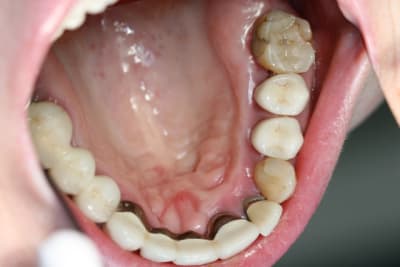

Bonjour, je sèche sur un cas, dont je vous joint le scan.

Je pensais m'en sortir avec des proth sur implants pour 13->11 et du classique par ailleurs.

Malheureusement, j'ai peu d'épaisseur osseuse en antérieur; j'ai par ailleurs peu d'expérience en greffe ou expansion : je n'en connais pas les limites et ne sais donc pas comment aborder mon cas...

Quant à la mandibule, elle est complètement dentée.